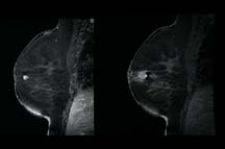

MRI-guided breast biopsy with the Suros ATEC system is viewed as one of the patient follow-up protoc

Lehman noted that when she first began doing breast MRI at the Seattle Cancer Care Alliance in 2003, targeted ultrasound was performed on all patients with suspicious lesions on MRI. “We’ve definitely shifted from that model and now proceed directly to MRI biopsy without a targeted ultrasound for some types of lesions,” she said. “We still do perform ultrasound-guided biopsies of MR lesions, but there are many cases we can’t do that and thus need MR biopsy capability in order to diagnose most accurately those lesions we see on MRI.”

“Ultrasound is a good method to biopsy when you see something under MRI that is seen on ultrasound as well,” Lehman said. “It’s more comfortable for the patient and a less costly procedure. However, cancers seen on MRI can be completely invisible on targeted ultrasound, and I’ve seen many examples of where MRI has detected DCIS or small invasive cancers that were missed on ultrasound. This is not just my personal experience, but can also be found in published data in peer-reviewed literature.”

What women are at risk for exhibiting lesions visible on MRI, but missed by targeted ultrasound? Women with breast tissue that is more fatty than dense and women with ductal carcinoma in situ (DCIS) seem to be at the highest risk of having cancers missed by ultrasound. Even the most ardent supporters of ultrasound don’t recommend imaging in fatty breast tissue due to the difficulty in finding small cancers, and it is well documented that ultrasound is not as effective as MRI or mammography in detecting DCIS. Women with prior surgery also fall into the high-risk category of having cancers missed by ultrasound. Tissue distortion from prior surgery can mask cancers on the ultrasound, and the sensitivity of MRI in detecting small cancers within regions of scarring is better than that reported with ultrasound.